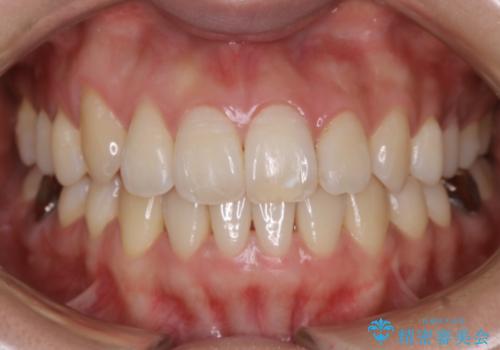

- 上下の歯のガタつきを主訴にご来院されました。

前歯部に特にガタつきが見られ、正中もズレている状態でした。

矯正装置の希望がインビザラインだったため、マイクロインプラントを併用し、奥歯から順に遠心移動をかけていくことにより非抜歯でも主訴のガタつきを治すことができました。

術前・術後の笑った時の歯の見え方の変化にも注目してみてください!

マウスピースとマイクロインプラントを組み合わせることで、抜歯をしなくても歯並びを治すためのスペースを作ることができます。奥歯から順に移動させていくので前歯に変化が出るまでには時間がかかりますが、その分健康な歯を抜歯することなく理想的な歯並びを手に入れることができます。